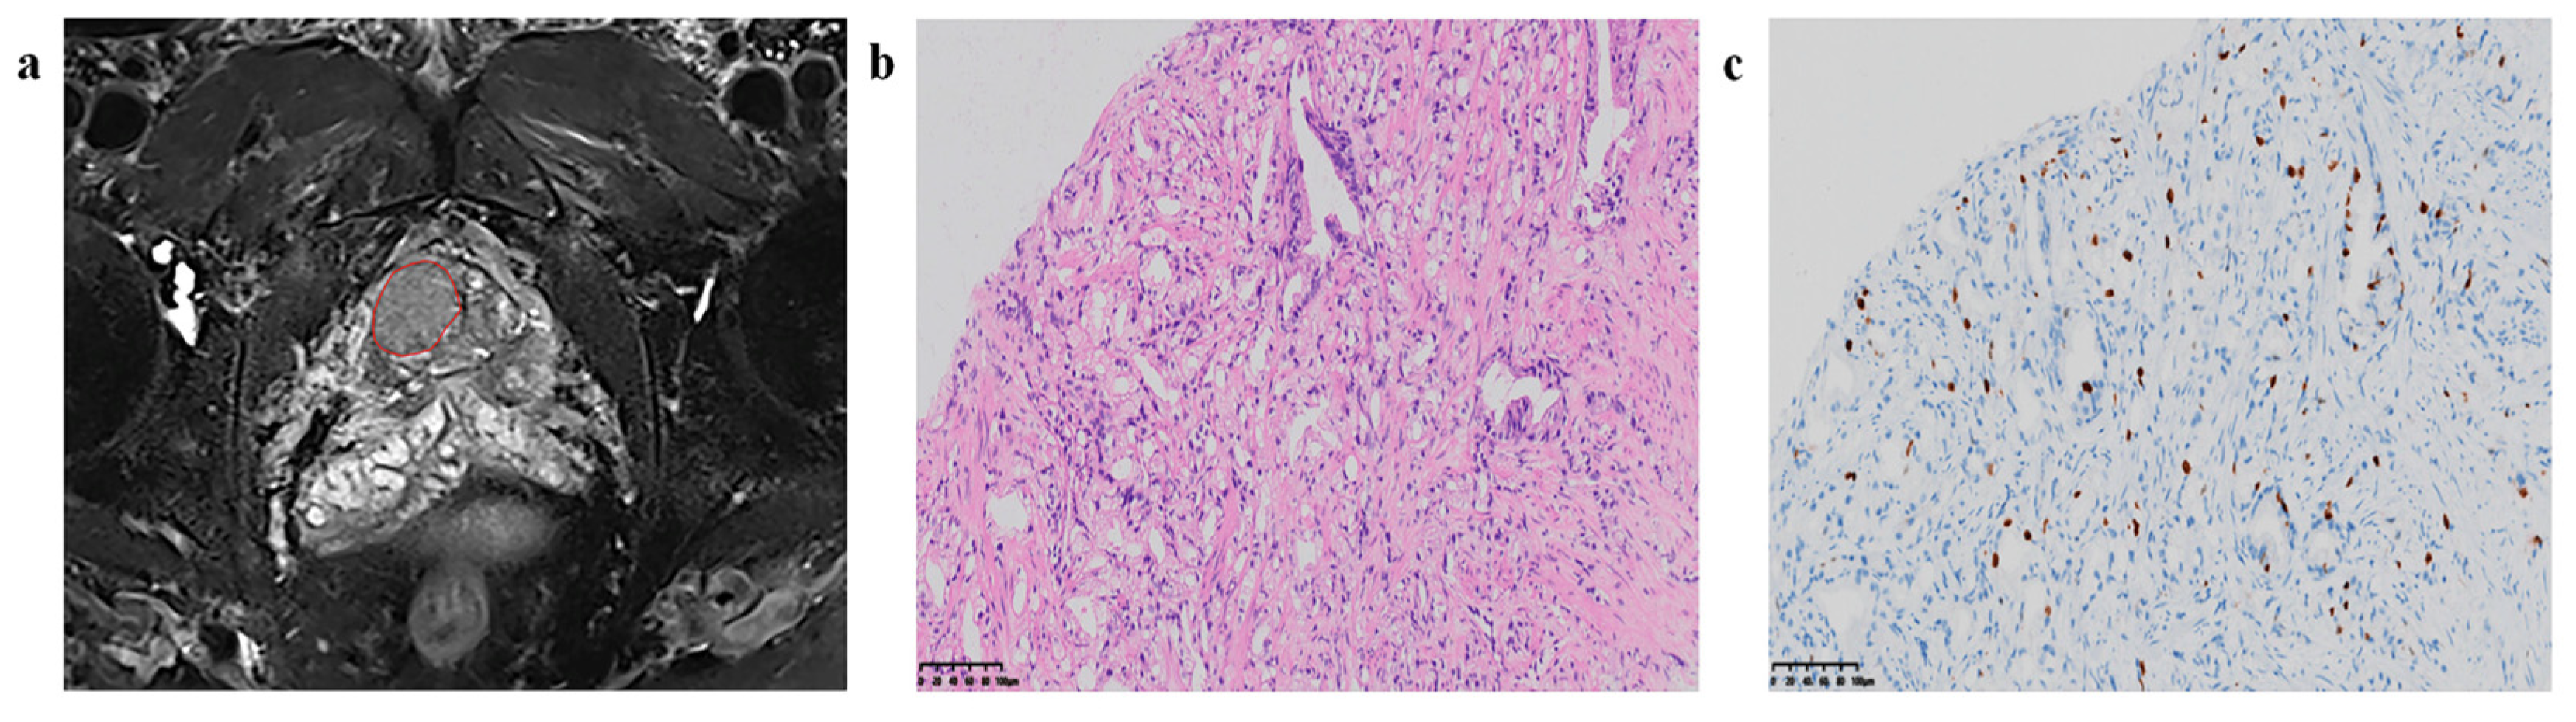

5. AI and Radiomics in Prostate Cancer

Development in Diagnostic and Prognostic Tools

- Prostate cancer management has been revolutionized by AI-augmented MRI, which has markedly improved tumor detection and localization. These advances, coupled with AI’s proficiency in prognosticating post-treatment trajectories, such as biochemical recurrence, are invaluable for patient-centric care.

- Woźnicki, P.; Westhoff, N.; Huber, T.; Riffel, P.; Froelich, M.F.; Gresser, E.; von Hardenberg, J.; Mühlberg, A.; Michel, M.S.; Schoenberg, S.O.; et al. Multiparametric MRI for Prostate Cancer Characterization: Combined Use of Radiomics Model with PI-RADS and Clinical Parameters. Cancers 2020, 12, 1767. [Google Scholar] [CrossRef]

- Qiao, X.; Gu, X.; Liu, Y.; Shu, X.; Ai, G.; Qian, S.; Liu, L.; He, X.; Zhang, J. MRI Radiomics-Based Machine Learning Models for Ki67 Expression and Gleason Grade Group Prediction in Prostate Cancer. Cancers 2023, 15, 4536. [Google Scholar] [CrossRef]

- Zhu, X.; Shao, L.; Liu, Z.; Liu, Z.; He, J.; Liu, J.; Ping, H.; Lu, J. MRI-derived radiomics models for diagnosis, aggressiveness, and prognosis evaluation in prostate cancer. J. Zhejiang Univ. B 2023, 24, 663–681. [Google Scholar] [CrossRef]

- Gentile, F.; La Civita, E.; Della Ventura, B.; Ferro, M.; Cennamo, M.; Bruzzese, D.; Crocetto, F.; Velotta, R.; Terracciano, D. A Combinatorial Neural Network Analysis Reveals a Synergistic Behaviour of Multiparametric Magnetic Resonance and Prostate Health Index in the Identification of Clinically Significant Prostate Cancer. Clin. Genitourin. Cancer 2022, 20, e406–e410. [Google Scholar] [CrossRef] [PubMed]